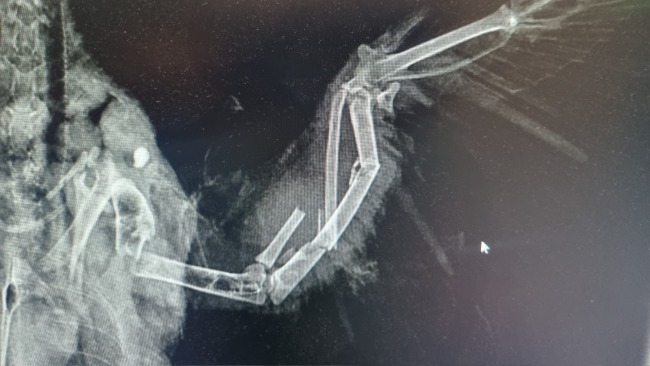

Właściciela posesji miała rację - ptak ma w sobie świeży śrut, który rozerwał mu jedno skrzydło, które jest całkowicie połamane. Dobrze się przyglądając, można zobaczyć ranę wlotową 😭😭😭

⚠️ Cel był celny. Tak jak okrucieństwo,, sadyzm, brak empatii, zwykłego zwyrodnialca, który z zabawy uczynić sobie okrutną rozrywkę. Oczywiście - z uwagi na dobre rokowania oraz sadystyczną krzywdę, której doznał, będziemy ratowali jego życie i sprawność. Patrzcie, jaki jest piękny i dobry dla ludzi.